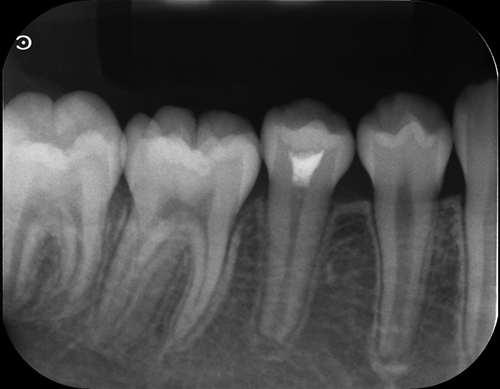

この症例は、生え変わり前に根管に膿が溜まっていた(赤で示した部分)ため。

その部分の除去を行いました。

治療を早期段階で行ったことで歯根もしっかり伸びました。

初期:膿が陰になっている

中期:膿が除去できているが歯根が短い

完了:膿もなく歯根もしっかり伸びている